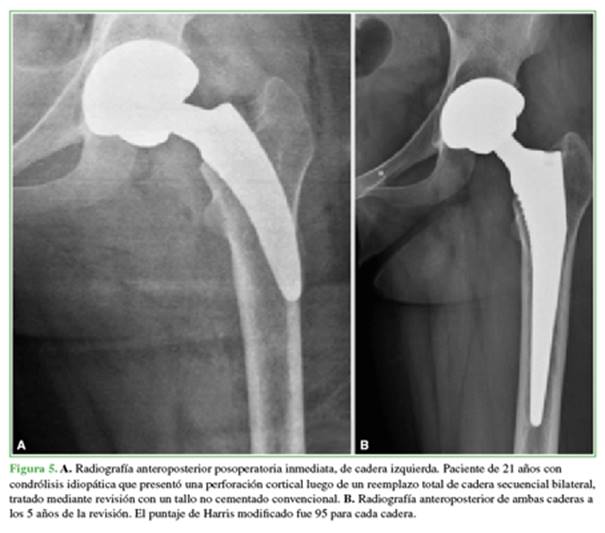

La supervivencia del vástago libre de falla aséptica fue del 99% (IC95% 93,1-99,8%) en un seguimiento promedio de 42 meses (rango 24-64) y del 98% cuando se incluyó la infección. Ningún paciente se perdió en el seguimiento. La principal complicación ocurrió en el caso 6 (enumerado en orden cronológico de inclusión en el estudio según la fecha de cirugía): una perforación de la cortical lateral (Figura 5A) que fue tratada el mismo día, durante la cirugía, con revisión del vástago corto a uno de longitud convencional de fijación metafisodiafisaria recubierto con hidroxiapatita (Figura 5B). Asimismo, se registraron tres fracturas intraoperatorias incompletas del calcar (3%), de las cuales una sola requirió de un cerclaje con alambre y descarga parcial durante los primeros 30 días posquirúrgicos.

La edad promedio de los pacientes fue de 46.7 años (rango 21-62); 38 pacientes eran de sexo masculino y 12, de sexo femenino. Los diagnósticos principales fueron artrosis degenerativa (42 casos), displasia del desarrollo de la cadera (5 casos), osteonecrosis (2 casos) y condrólisis idiopática (1 caso). Todos los implantes fueron colocados por el mismo cirujano a través de un abordaje posterolateral con anestesia raquídea.